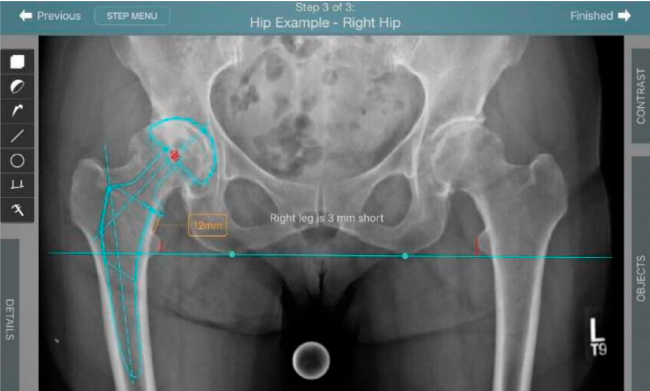

Planeación preoperatoria mediante la creación de plantillas digitales para reemplazo de cadera y análisis intraoperatorio

Anotaciones digitales y herramientas de análisis de longitud de pierna.